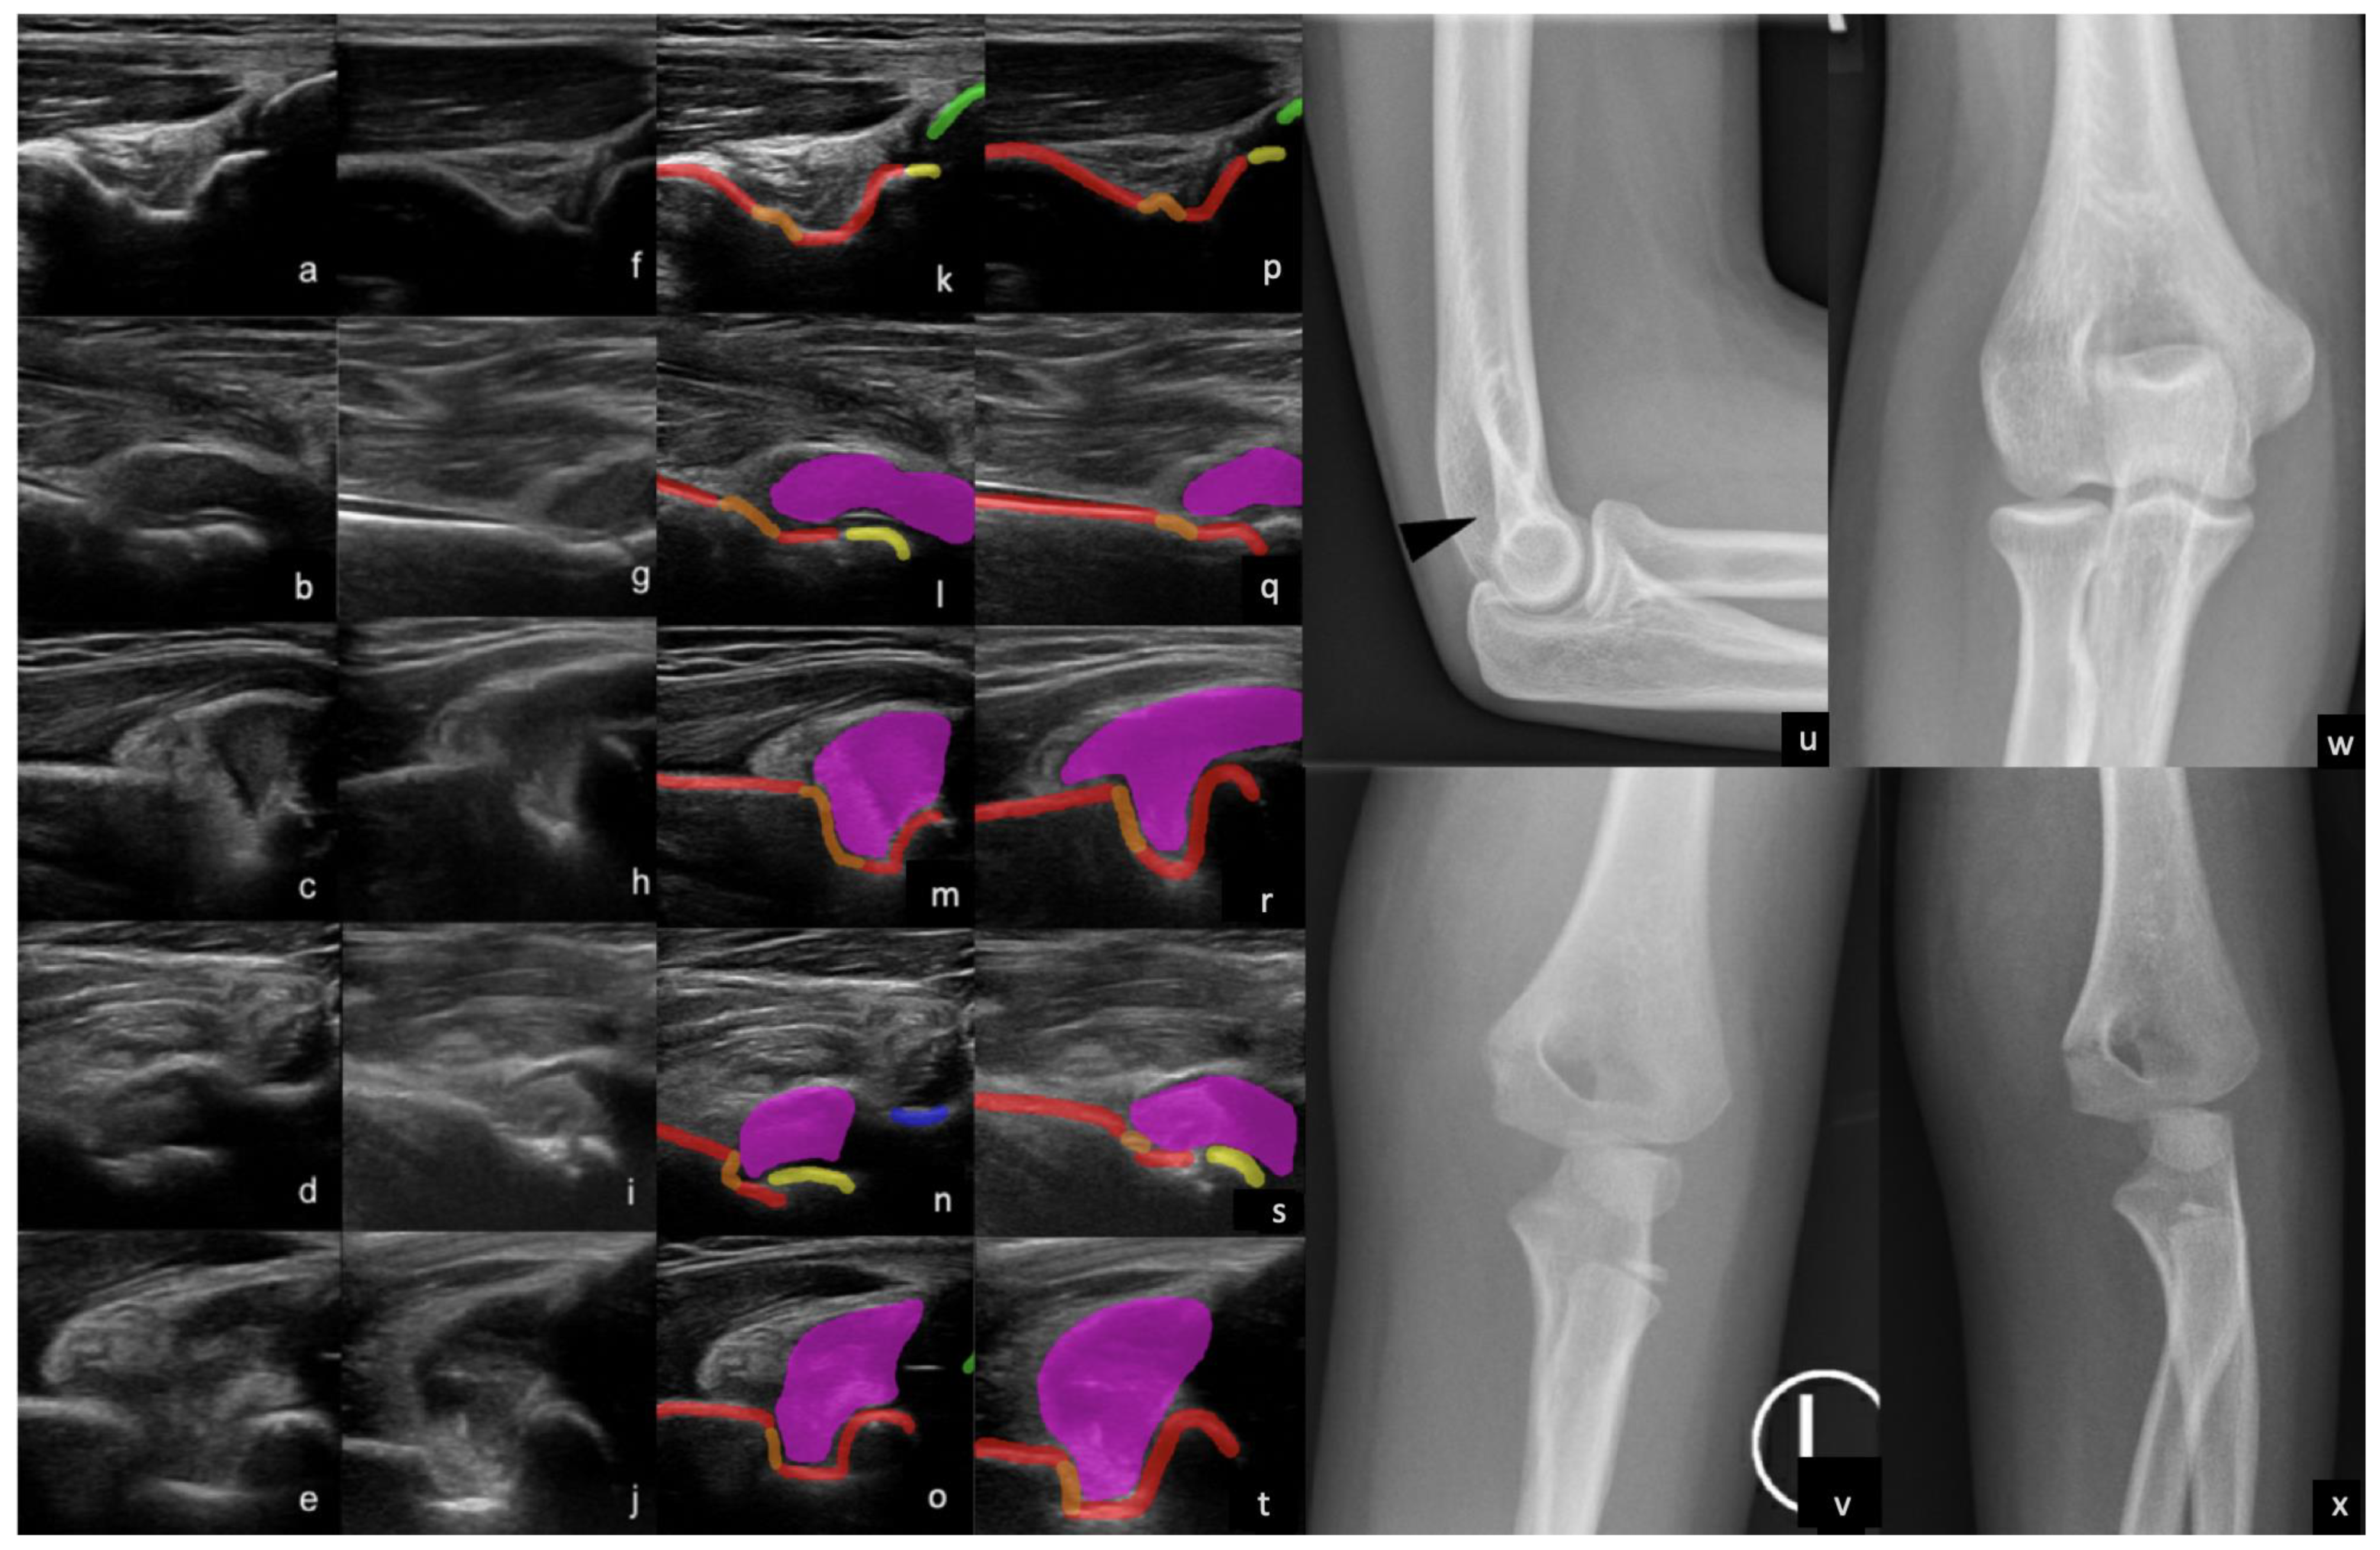

Figure 3.

Examples of supracondylar fractures and elbow effusions with anatomy labels superimposed (red = humerus, orange = fracture, yellow = capitellum/trochlea, green = ulna, blue = radius, magenta = effusion). Buckle fracture on a dorsal 2D (a) and 3D (f) US images, with corresponding labels (k,p). Cortical step deformity, effusion, and fat pad elevation representing a fracture on a volar 2D (b) and 3D (g) US image, with corresponding labels (l,q). Sharp step of the olecranon fossa, effusion, and fat pad elevation suggestive of a supracondylar fracture on dorsal 2D (c) and 3D (h) US images, with corresponding labels (m,r). Subtle cortical interruption and effusion representing a minimally displaced fracture on volar 2D (d) and 3D (i) US image, with corresponding labels (n,s). Subtle cortical discontinuity in the superior aspect of the olecranon fossa representing the fracture on dorsal 2D (e) and 3D (j) US images, with corresponding labels (o,t). Radiographs (u,w) corresponding to the 2/3D US images (a,f,k) and (p). Note the subtle contour irregularity in the olecranon fossa cortex (black arrow head), which is suspicious for a buckle fracture and much more readily apparent on US. Radiographs (v,x) corresponding to (b,g,l) and (q) 2/3D US images demonstrating the fracture line. Note the marked soft tissue swelling. This patient was unable to flex their elbow; though an effusion is highly suspected, it is not actually demonstrated on radiographs, but can be easily observed on both volar and dorsal 2/3D US images.